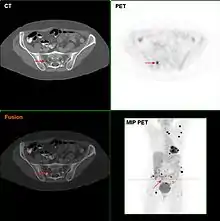

F18-FDG PET/CT in a melanoma patient showing multiple lesions, most likely metastases

Metastatic melanomas can be detected by X-rays, CT scans, MRIs, PET and PET/CTs, ultrasound, LDH testing and photoacoustic detection.[90] However, there is lack of evidence in the accuracy of staging of people with melanoma with various imaging methods.[91]